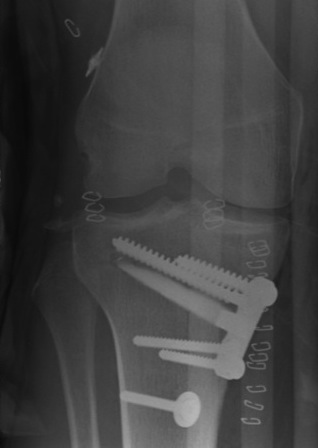

Technique

- medial opening wedge with plate and allograft bone

- correct so that mechanical axis passes through down slope of lateral tibial spine

ACL + High tibial osteotomy for ACL + chronic posterolateral corner

ACL / Posterolateral corner / patient in varus

ACL + high tibial osteotomy